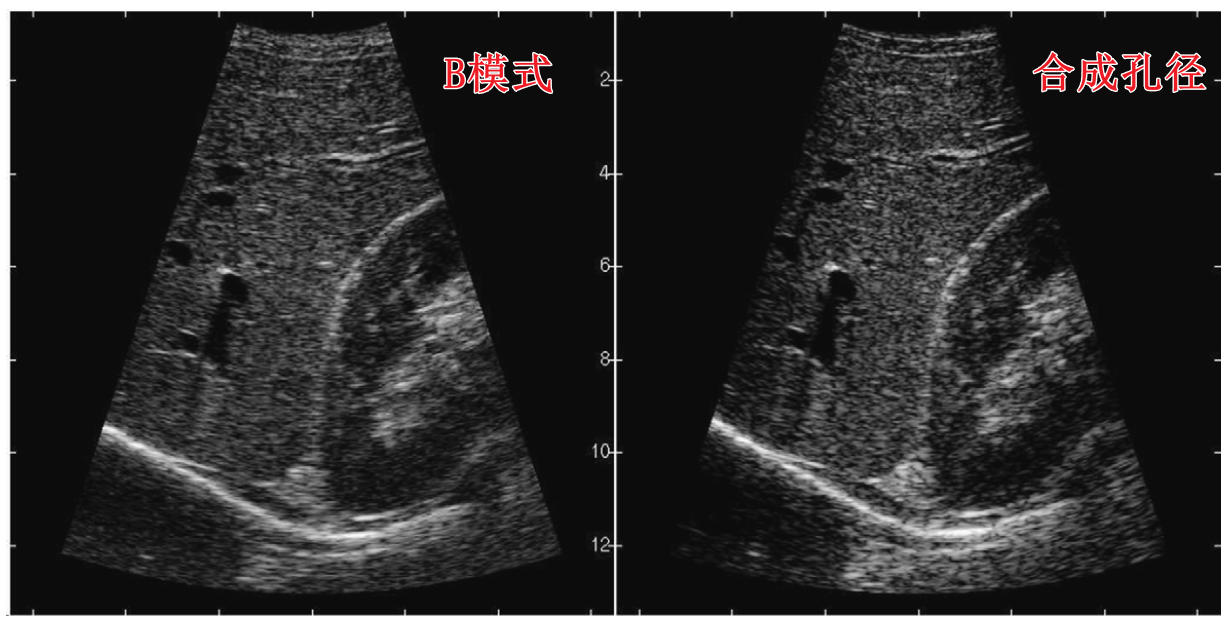

1.2.1 合成孔径成像SA

合成孔径成像启发于雷达的合成孔径,传统合成孔径成像可以参考jensen2006年的综述:Synthetic aperture ultrasound imaging - ScienceDirect

其使用一个一个阵元分别激励,使用全孔径接收,比如128阵元,就会产生128帧RF数据,之后在经过波束形成进行成像。

通过单个阵元激励合成孔径成像效果还是提升很大的